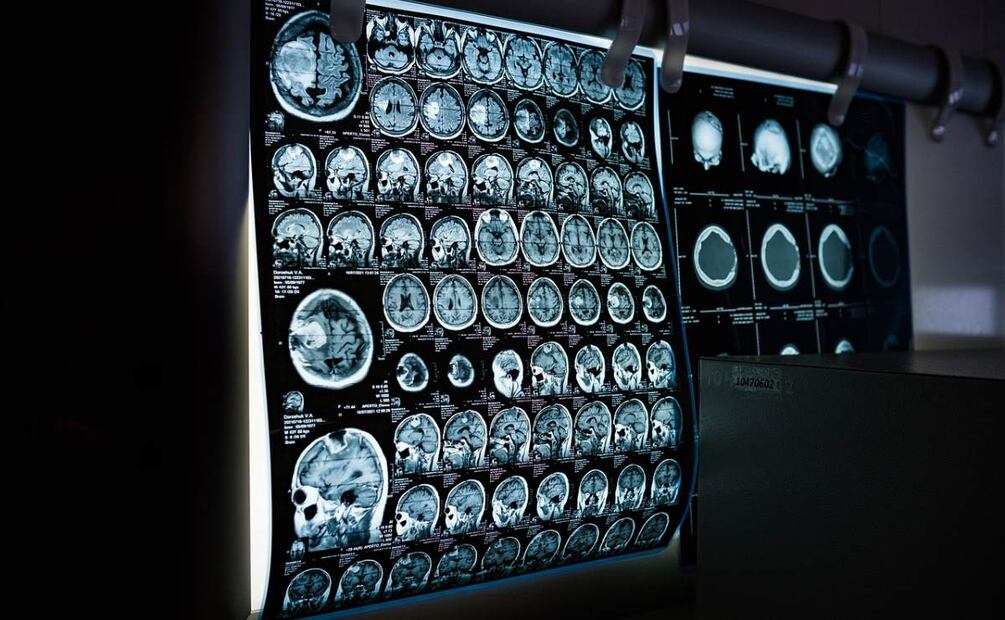

Si bien el cantante Michael Bolton no ofreció mayores detalles sobre las pruebas que le fueron aplicadas para la detección del tumor cerebral, Medline detalla que hay una serie de pruebas que se le pueden aplicar a los pacientes que presentan síntomas.

- Tomografía computarizada de la cabeza

- Resonancia magnética de la cabeza